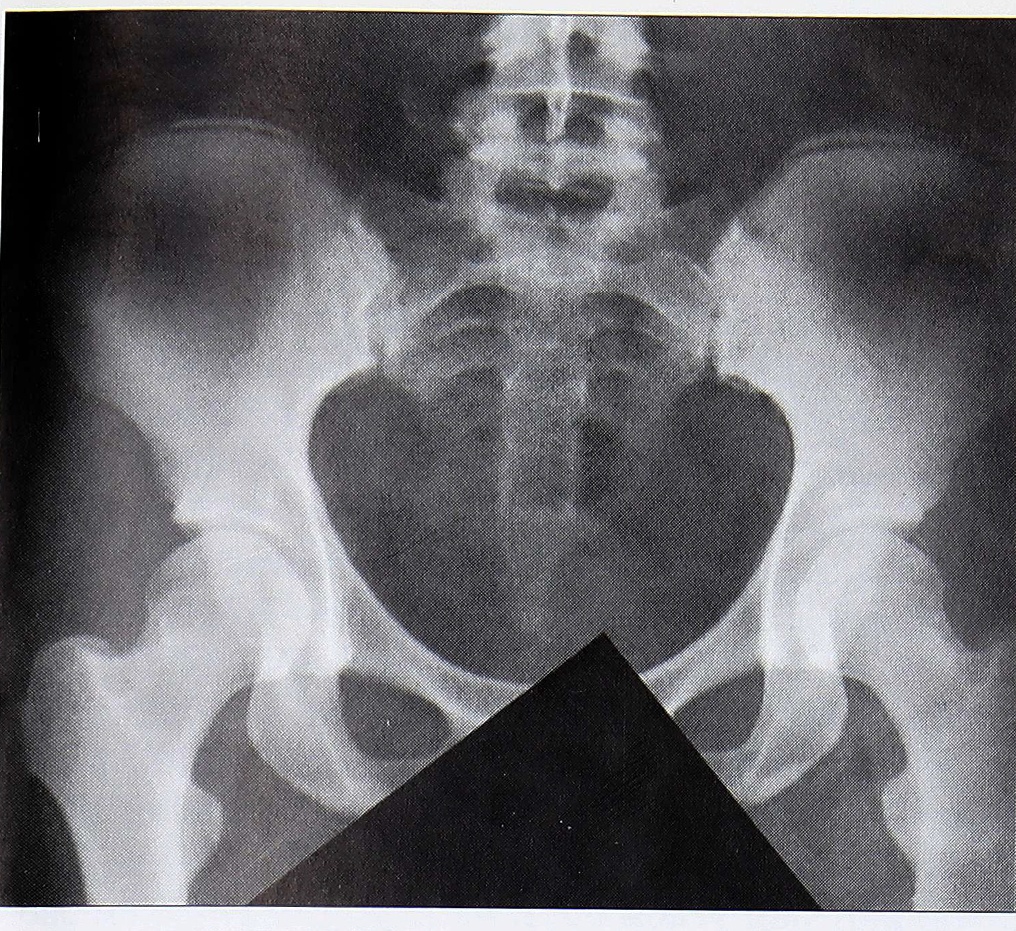

Рис. 4. Рентгенологическая картина тракционного апофизита ( больная 25 лет, солистка балета).

При рентгенологическом обследовании в большинстве случаев определялись диспластические изменения в пояснично-крестцовом отделе — люмбализация или сакрализация, незаращение дуг крестцовых позвонков, аномалии тропизма, высокая ассимиляция таза с круто и высоко стоящим крестцом, малым основным углом и малым подвздошным прикрытием. В 4 случаях отмечены явления тракционного апофизита подвздошной кости, что выражалось в отсутствии оссификации апофиза ее крыла у пациентов старше 20 лет (рис. 4). У 7 больных выявлен периостит крыла подвздошной кости.